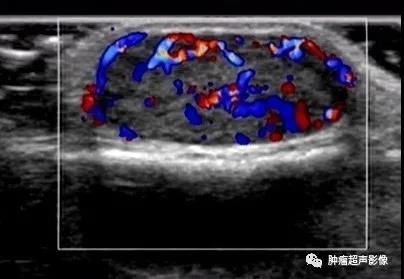

病理证实的血管平滑肌瘤,下肢、单发、可移动的疼痛结节,超声表现为皮下边界清的椭圆形低回声肿块(内见无回声),包膜完整,血流丰富,符合典型血管平滑肌瘤。